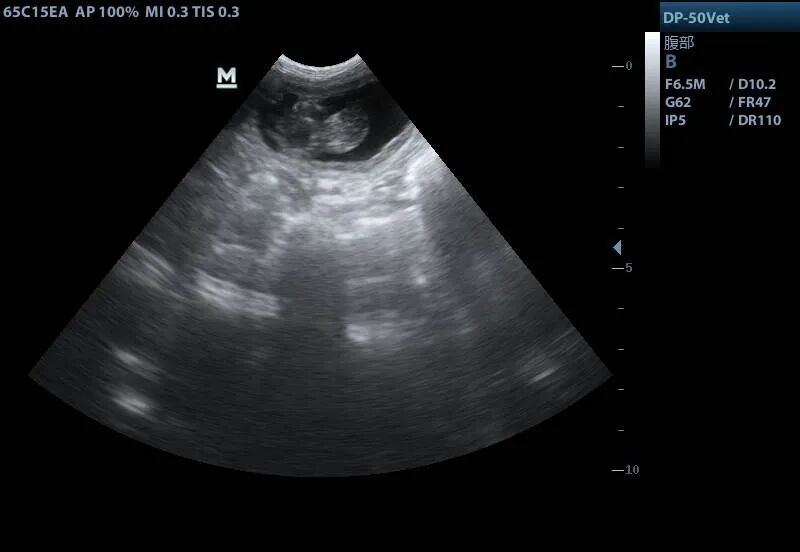

妊娠中の代理出産メス猫の超音波画像。画像提供は青島農業大学